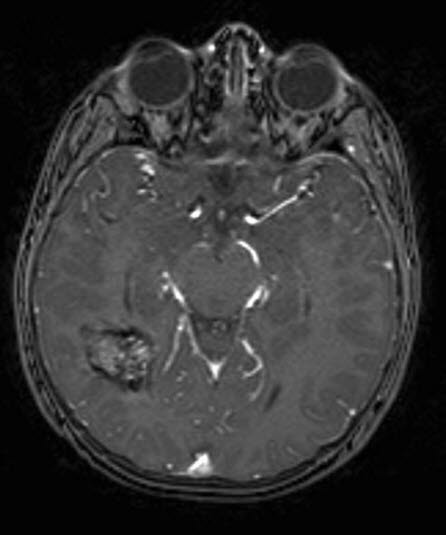

Kavernøst hemangiom, aksialt snitt 1

kavernøst hemangiom 1

Gjengitt med tillatelse av Radiologisk avdeling, Universitetssykehuset Nord-Norge